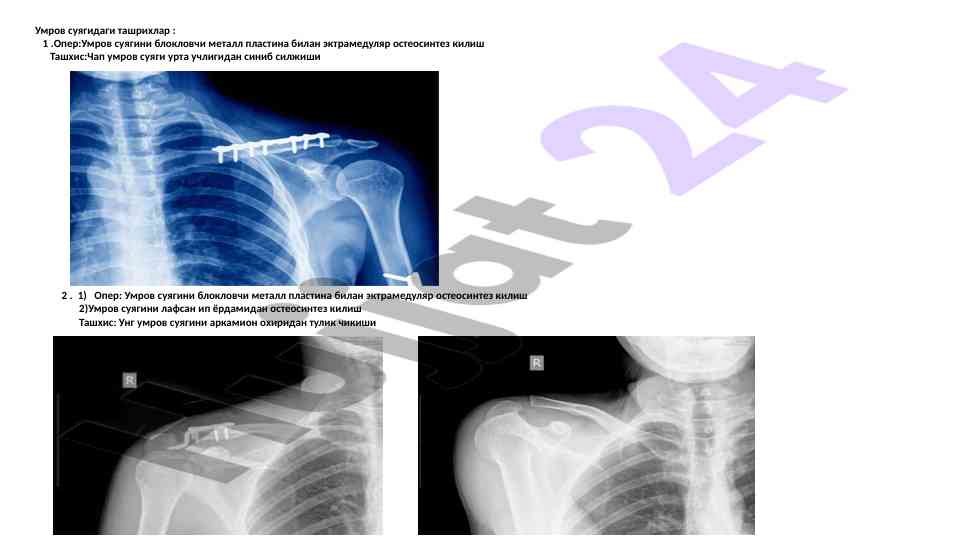

Ushbu ilmiy maqola zamonaviy travmatologiya asoslari, jarohatlarni diagnostika qilish va davolash usullarini takomillashtirish haqida ma'lumotlar taqdim etadi.